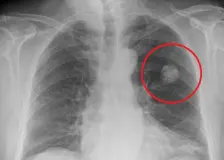

PCR test: jak funguje a co ukazuje?

PCR test je vysoce citlivá laboratorní metoda, která slouží k detekci konkrétního genetického materiálu (DNA nebo RNA). Používá se zejména k diagnostice infekčních onemocnění, genetických poruch a některých typů nádorových onemocnění. Pozitivní výsledek znamená, že byl ve vzorku nalezen hledaný genetický materiál, negativní výsledek jeho přítomnost neprokázal. Mezi hlavní výhody PCR testu patří vysoká přesnost, Continue Reading The post PCR test: jak funguje a co ukazuje? first appeared on Reha…